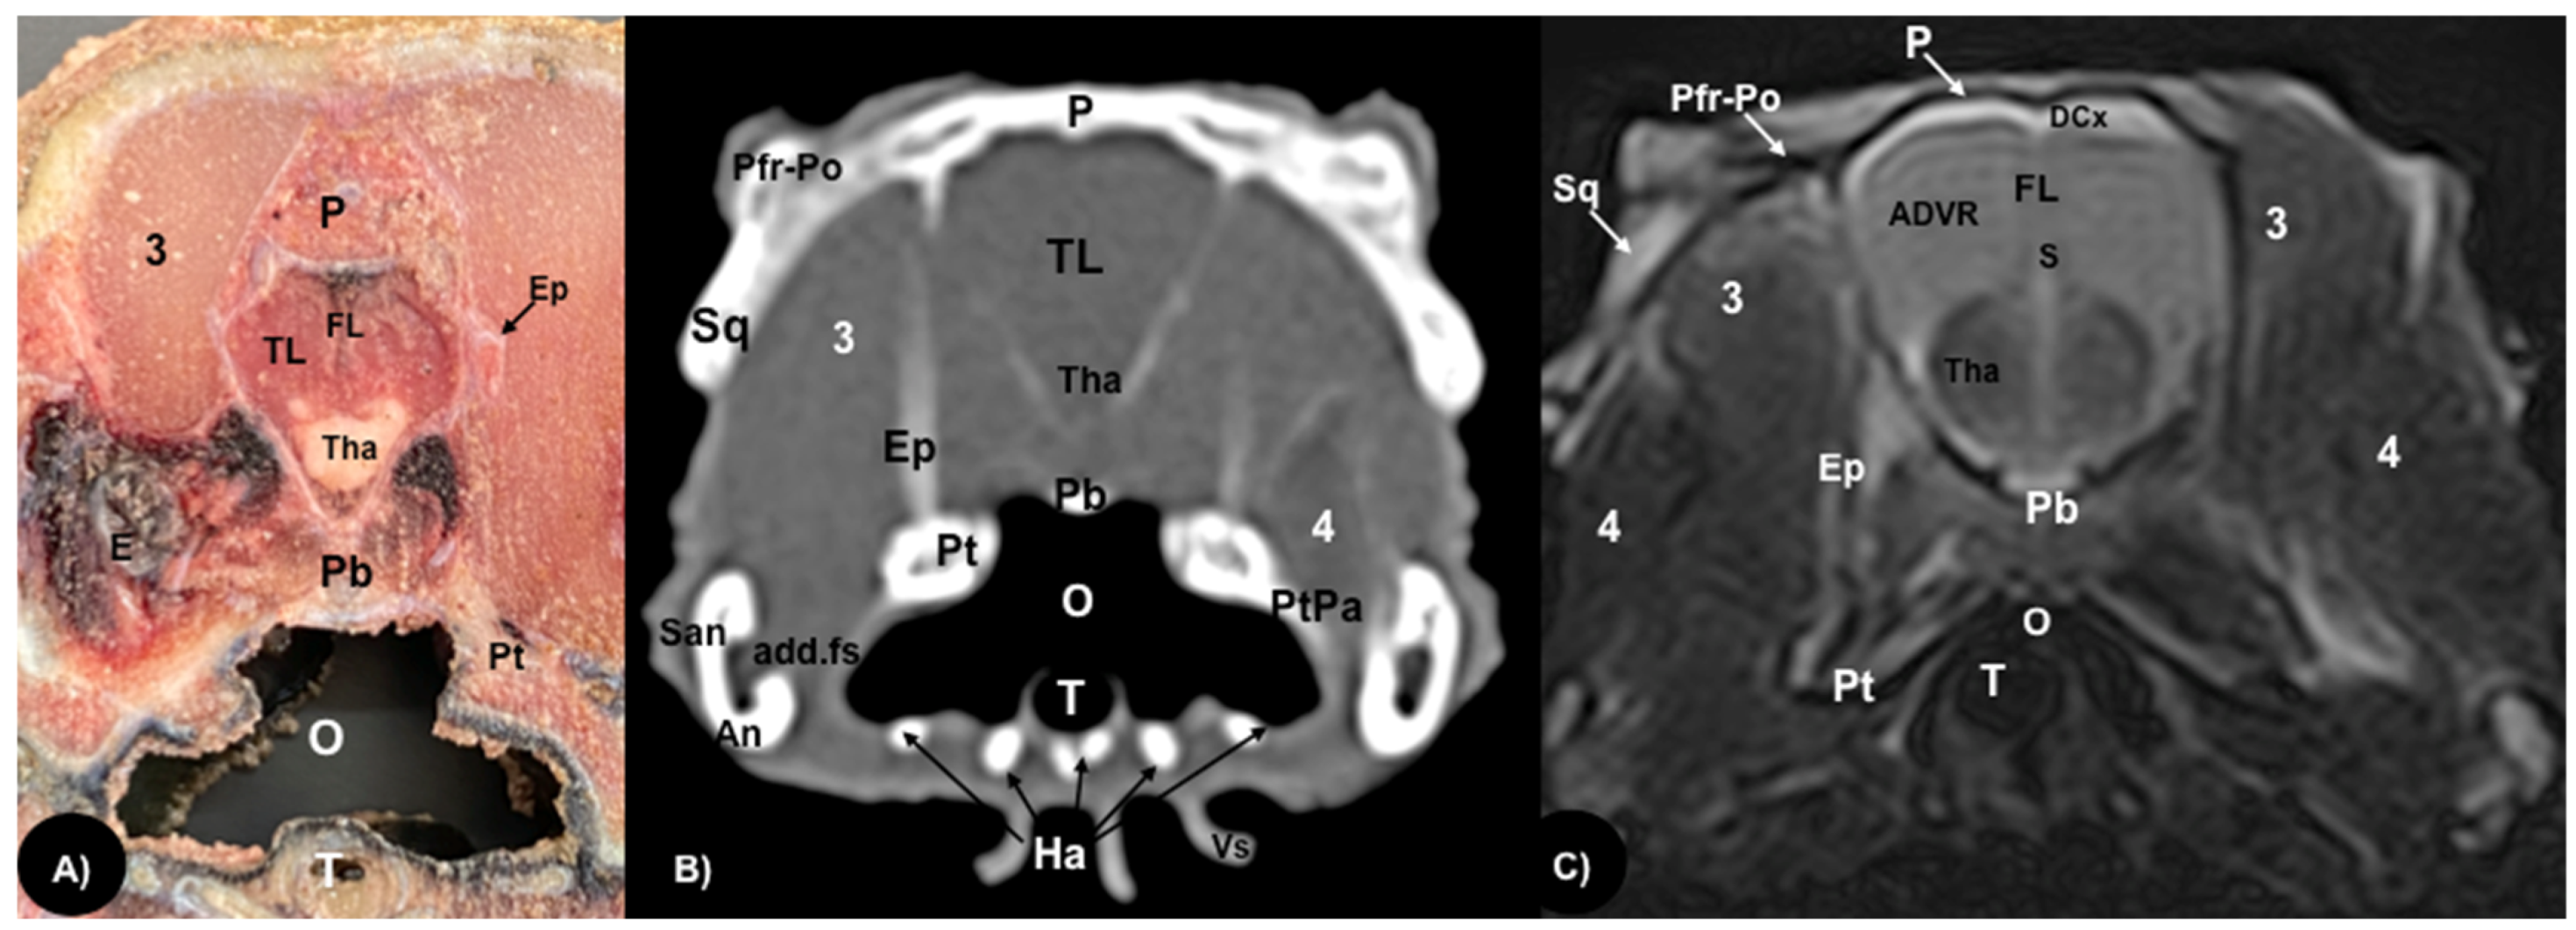

3.1. Anatomical Sections

3.2. Computed Tomography (CT)

3.3. Magnetic Resonance Imaging (MRI)